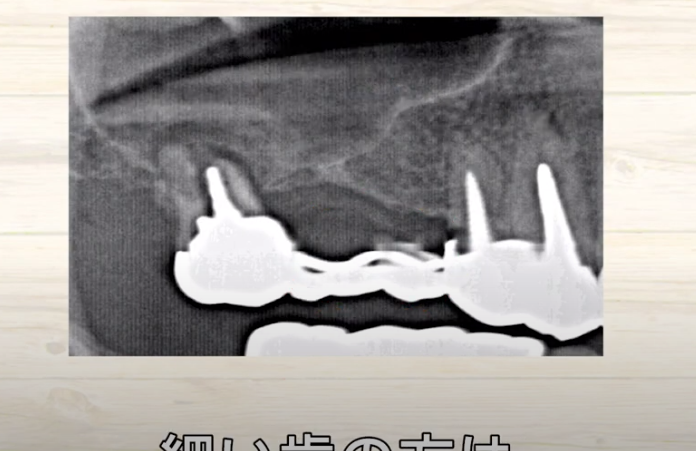

別の方のCT写真です。

歯の頭の位置で

輪切りではなく

縦に切って撮影した写真です。

ここに黒い部屋があります。

ここは鼻の部屋です。

つまり

硬いものが白くうつるわけですから

空気がある

鼻の部屋ですから

空気があるわけです。

指している

空気がないといけないところに

何かうつっていますね?

何かが鼻の中にある

というところですね。

副鼻腔

上顎洞の中の場所になりますので

副鼻腔炎

という病名がつきます。

もっと見てみると

少し歯の根っこが

鼻の部屋に入り込もうとしています。

こちらはどうでしょうか?

完全に鼻の中に

歯の根っこがめり込んでしまっています。

硬い骨があって

歯の根っこがどんどん

突き上げられていって

突き抜けている

ということが

わかります。